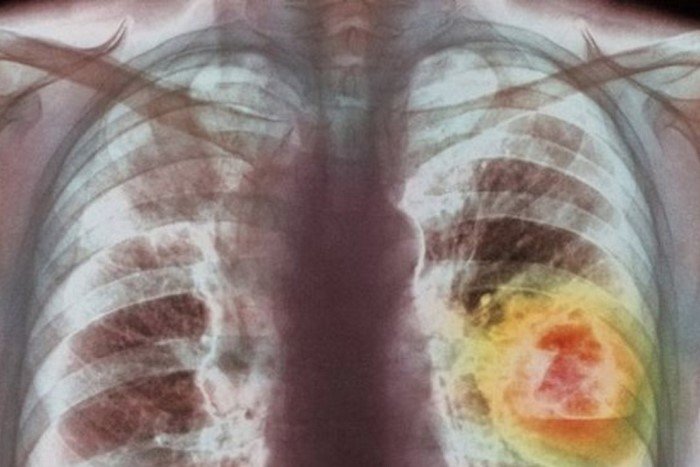

Циклы химиотерапии следовали один за другим. Позже медикам пришлось провести ампутацию ноги. Но метастазы опухоли уже дошли до легких.

Врачи насчитали 28 метастаза в правом и целых 42 — в левом легком. Но тут за обреченную казалось бы девушку взялся лично Евгений Левченко. Через много лет именно спасение Ирины принесет ему ту самую премию.